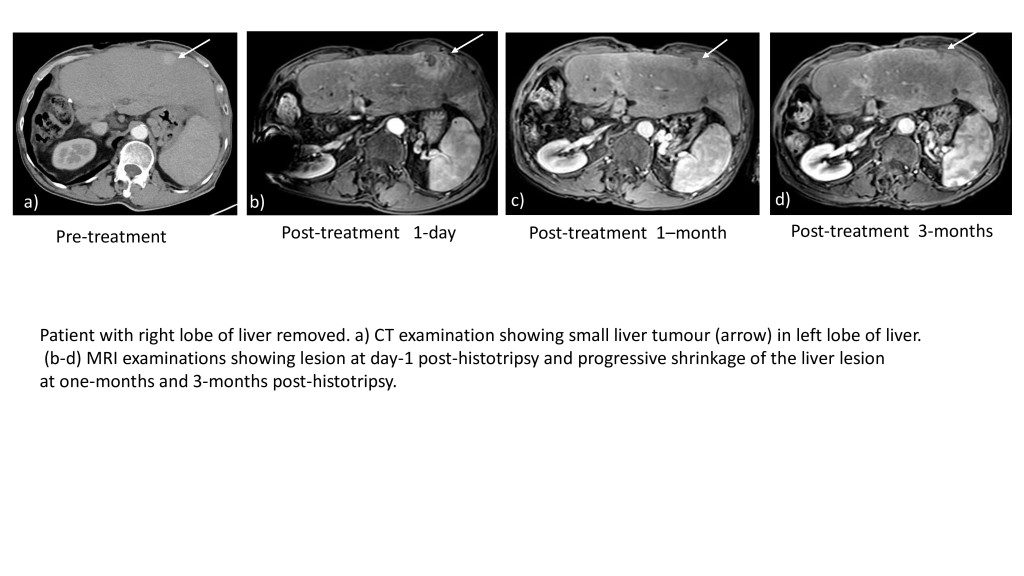

本港目前的Histotripsy儀器均在私家醫院運用。今年4月引入儀器的中大醫院,至今處理26宗個案,當中25名患者適合且已成功進行療程,整體成功率逾96%。68歲的病人陳先生(化名)指,患上肝癌約10年,一直未能斷尾,曾做過開刀手術、放射治療、微波消融術、肝動脈化療栓塞法等不同療法,至今年2月左肝肝癌再復發後,4月便在李嘉誠基金會資助下嘗試用Histotripsy治療。他指,療程全長約30至45分鐘,亦成功消滅腫瘤,「新療法無創無痛,治療隔日便可出院和進食,較其他治療方案更令人安心。」

中大醫學院外科學系肝膽胰外科組主任竺兆豪表示,Histotripsy治療成效理想,副作用包括發燒、短暫血壓高等,相當輕微,「通常觀察一晚,隔日都慢慢恢復正常」。他指,陳先生的腫瘤少於3厘米,且可做全身麻醉,條件合適故獲推薦做Histotripsy,「坦白說,他做過那麽多治療,都想做些不那麽痛、住院日子減少、沒有傷口、併發性減到最少的治療」。